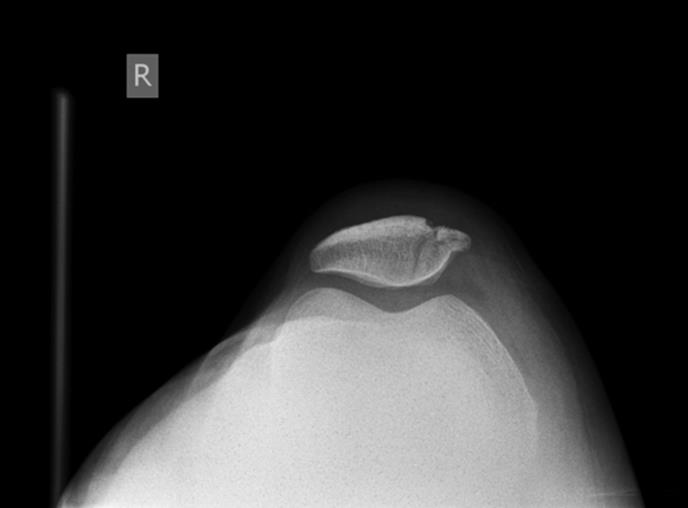

· A “sunrise” or “skyline” view can increase the sensitivity for a patellar fracture (Figure 4.1)

Figure 4.1 “Sunrise” or “skyline” view: Additional view that can increase sensitivity of the radiograph for patellar fractures. Here a fracture is noted. (Image courtesy of Arun Sayal, MD.)